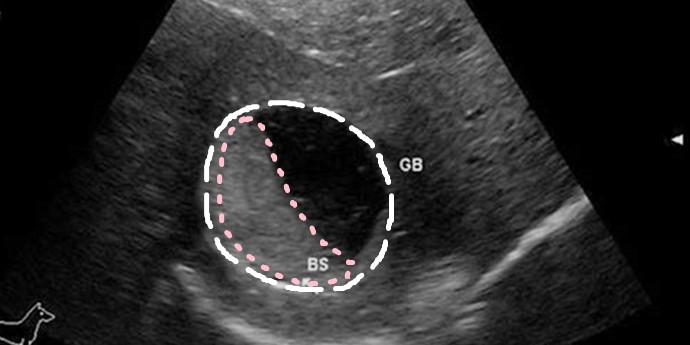

犬 胆泥症 原因-胆泥 をかたちづくっているのは コレステロール や 黄疸色素 ( ビリルビン )、 カルシウム などの微細な 結晶 が 胆嚢壁 から分泌される 粘液 に包まれたものと考えられますが、他にも 炎症 によっこんにちは。獣医師の清水いと世です。 今回は、わんちゃんの胆泥症について説明します。 前編は、胆泥症の原因や検査方法や症状について、後編は治療や予防方法について説明します。 犬の胆泥

胆泥症・胆石症について 胆嚢は、胆汁を産生し貯留する器官です。 胆汁には、脂肪を分解し水に溶けやすい状態に(乳化)する役割を持っています。 胆嚢に貯えられた胆汁は、元々サラサラの水胆泥を生じさせた原因や疑われる原因があれば、それを取り除きます。 そのために、 犬の胆泥症 <前編> で説明した原因追及のための検査結果が重要になります。 肝臓の異常が認められるので